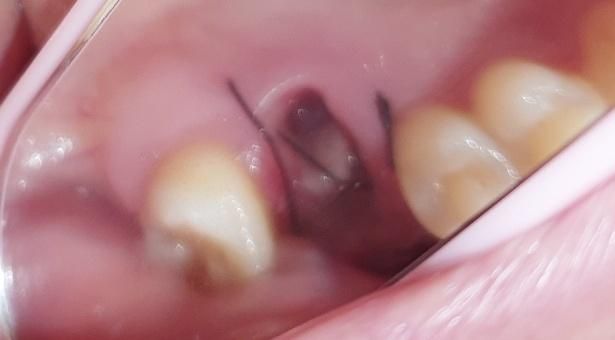

발치 후 구멍이 깊은데 관리를 어떻게 해야하는지 알려주세요

발치한지 하루 지나서 구멍에 음식물이 낀줄 알고

병원갔었는데 혈병? 이라고 하셔서 그냥 집에 왔고

집에와서 보니 떨어지고 안이 그대로 보이는데

괜찮은건가요?ㅠㅠ

구멍이 깊어서 음식물 끼이면 안빠질까봐

밥을 먹질 못하겠어요ㅠ

어떻게 관리해야하나요??

• 1번 째 사진